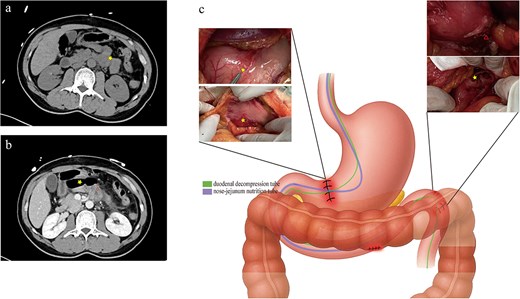

At approximately midnight on a rainy night, a 42-year-old man presented to our emergency department around half an hour after falling from his electric bicycle on a slippery road. The handlebars struck his left lower chest and left upper quadrant, and he complained of persistent pain in the left upper abdomen. On examination, there were small contusions over the left costal margin, marked tenderness in the left upper quadrant with mild rebound, and no signs of hemodynamic instability. Initial laboratory studies revealed a mild anemia (hemoglobin 11.6 g/dl), and contrast-enhanced computed tomography (CT) demonstrated multiple left-sided rib fractures, slight peripancreatic fluid collection, and subtle edema of the proximal jejunum (Fig. 1a). The patient was admitted for observation by the surgical team. Eight hours later, repeat contrast CT revealed extraluminal air and contrast leakage at the junction of the ascending duodenum and proximal jejunum, consistent with perforation (Fig. 1b), and he was taken for emergent laparotomy. Intraoperatively, injuries to the stomach, transverse colon, ascending duodenum, and proximal jejunum were confirmed (Fig. 1c).

(a) Initial non–contrast abdominal CT on presentation demonstrating slight peripancreatic fluid collection, mild wall thickening, and edema of the proximal jejunum (yellow star). (b) Contrast-enhanced CT performed 8 hours later, showing extraluminal air (yellow star) and contrast leakage (red triangle) at the junction of the ascending duodenum and proximal jejunum. (c) Intraoperative view showing serosal lacerations of the stomach and transverse colon, with perforations of the ascending duodenum and proximal jejunum (yellow star denotes the main defect; red triangle indicates a smaller perforation identified endoscopically), and the positions of the duodenal decompression tube (purple) and nasojejunal feeding tube (green).

Serosal repair was performed on the stomach and transverse colon, and the duodenal and jejunal perforations were closed primarily. Intraoperative endoscopy facilitated placement of a nasojejunal feeding tube and a duodenal decompression tube. The feeding tube tip was positioned 20 cm distal to the repair site, while the decompression tube tip was advanced to the horizontal portion of the duodenum (Fig. 1c). The patient resumed oral intake 1 week postoperatively. A follow-up endoscopic examination prior to discharge confirmed complete mucosal healing (Fig. 2).